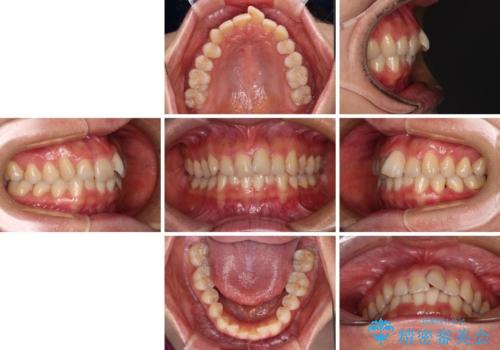

- 上下前歯のデコボコを気にして来院された患者様です。

叢生は軽度で、ワイヤー矯正でもマウスピース矯正でも対応可能な歯列でした。

僅か1年間できれいに歯列を整えることができ、患者様には大変満足していただきました。